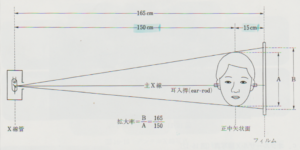

セファロは次のような規格が定められています。

・エックス線を照射する場所から被写体までの距離

・被写体からフィルムまでの距離

・エックス線を照射する場所からフィルムまでの距離

この3つの事が定められています。

(第3版 歯科矯正学より)